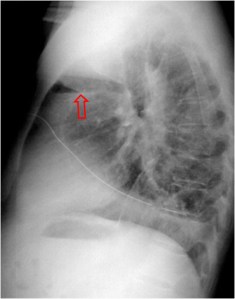

SIGNO DE LA CISURA INCOMPLETA, DE LA PSEUDOCAVIDAD O SIGNO DE LA ESPINA DE ROSA

Es un signo de derrame pleural en la cisura mayor visible en la radiografía de tórax, en un paciente con cisura mayor incompleta. Es más frecuente verlo en el lado derecho ya que en el izquierdo la silueta cardiaca puede ocultarlo.

La presencia de una zona radiotransparente perihiliar, circunscrita lateralmente por una línea curva bien marcada (flecha blanca), en cuya periferia se observan varios grados de opacidad, corresponde a la presencia de líquido en la cisura mayor incompleta. La línea curva termina en un extremo en punta (flecha roja), que estará más cercana al hilio cuanto más completa sea la cisura.

El nombre de pseudocavidad hace referencia a la radiolucencia perihiliar, mientras que el de espina de la rosa se refiere a la morfología de la opacidad, con el extremo en punta.